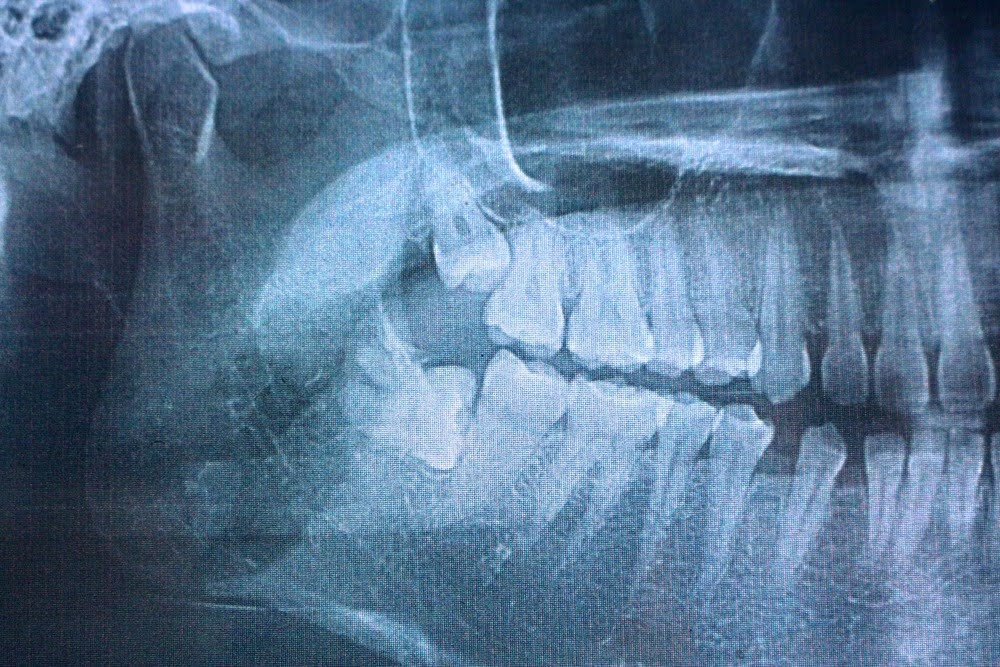

Wisdom teeth are the third set of molars, positioned at the very back of your mouth on the upper and lower arches. They typically erupt between the ages of 17 and 25, which is how they earned the nickname "wisdom teeth."For most people, the jaw simply does not have enough room to accommodate these late arrivals. When wisdom teeth cannot erupt properly, they become impacted, meaning they remain trapped beneath the gum line or emerge at an angle that pushes against neighboring teeth. The results range from mild discomfort to serious infection, cyst formation, and structural damage to adjacent teeth.

Not every wisdom tooth needs to come out. Dr. Burton evaluates each patient individually using advanced digital imaging to assess the position, angle, and relationship of the wisdom teeth to surrounding structures. If your wisdom teeth are fully erupted, properly aligned, and not causing any issues, monitoring may be all that is needed. But when problems are present or likely to develop, extraction is the right call.

- Impaction: The tooth is fully or partially trapped beneath the gum and bone and cannot erupt naturally

- Improper angulation: The tooth is growing at an angle toward the adjacent molar, creating pressure that can damage that tooth's root

1. Consultation and imaging: Digital X-rays and a clinical exam assess the position of the wisdom teeth and identify any complications that need to be addressed